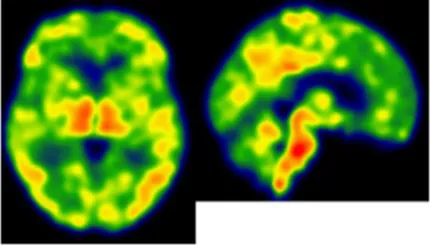

On an individual level, we observed a complex dissociation as the neuroinflammatory PET profiles appeared not to be predictive of patients’ clinical profiles and vice versa (Table 2): some patients with similar clinical presentations had opposed patterns of neuroinflammation, while other patients with opposite clinical presentations showed similar patterns of neuroinflammation.

Table 2

| Clinical findings | CSF and APOE | SWI and T1-weighted MRI scans | Proposition of ongoing neuroinflammatory processes |

|---|---|---|---|

| Case 5: a 64 y.o. man who was referred for a memory complaint. At screening, he had 24/30 MMSE and impairment on episodic memory, denomination and categorical verbal fluency tests. On MRI, multiple lobar microbleeds without hemisiderosis were observed as well as WMH (Fazekas’s score of 8/9) and moderate cortical atrophy. | Aβ42: 208 P-tau: 184 T-tau: 1449 APOE E3/E3 TSPO MAB | ![]() | ![]() Toxic neuroinflammation associated with mixed angiopathy and AD pathological progression. |

| Case 21: a 59 y.o. woman with early onset symptoms and familial history of AD. At screening, she had 23/30 MMSE and impairment on episodic memory, executive functions, processing speed and categorical verbal fluency tests. Three lobar microbleeds, WMH (Fazekas’s score of 3/9) and moderate cortical atrophy were observed on MRI. | Aβ42: 462 P-tau: 140 T-tau: 768 APOE E3/E4 TSPO MAB | ![]() | ![]() Low cortical neuroinflammation compared to the cerebellar cortex. |

| Case 2: a 66 y.o. woman with familial history of AD who was referred for a memory complaint. At screening, she had 30/30 MMSE, preserved memory, executive functions and processing speed but encoding impairment in visual recognition memory as well as decreased scores on long-term forgetting tests. Two lobar and one deep microbleed without hemosiderosis, WMH (Fazekas’s score of 5/9) and moderate cortical atrophy were observed on MRI. | Aβ42: 327 P-tau: 79 T-tau: 479 APOE E2/E4 TSPO HAB | ![]() | ![]() Protective neuroinflammation that might be compensatory to the amyloid load in the frontal and cingulate regions in the absence of spread tau pathology and neurodegeneration. |

| Case 12: a 64 y.o. man with early onset atypical AD in a posterior cortical atrophy variant. He presented a familial history of AD. At screening, he had 21/30 MMS, multi-domain cognitive impairment, especially constructive apraxia and visual apperceptive agnosia. WMH (Fazekas’s score of 5/9) and cortical atrophy were observed on MRI. | Aβ42: 481 P-tau: 103 T-tau: 669 APOE E3/E3 TSPO HAB | ![]() | ![]() Toxic neuroinflammation associated with AD pathological progression, especially in posterior cortical regions. |

Dissociation between clinical and neuroinflammatory PET profiles in early AD.

All fourth patients are right-handed. TSPO PET imaging showed SUVR relative to the cerebellar cortex and is represented in standard space in the same slice and intensity scale, whereas MRI scans are shown in native space. Cerebrospinal fluid AD biomarker values were abnormal for the four patients (see the method section for details).

Aβ42, amyloid-β 42; AD, Alzheimer’s disease; APOE, apolipoprotein E; CAA, cerebral amyloid angiopathy; CSF, cerebrospinal fluid; MMS, mini-mental state examination; MRI, magnetic resonance imaging, P-tau, phosphorylated tau; SWI, susceptibility-weighted imaging; T-tau, total-tau; TSPO, translocator protein; WB, whole brain; WMH, white matter hyperintensities.